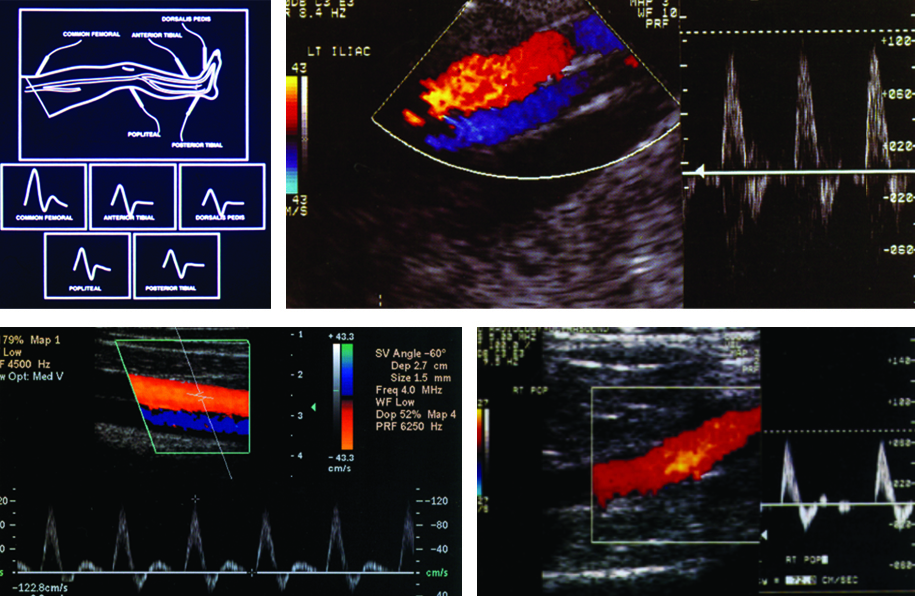

El examen de las arterias de los miembros inferiores comienza por el sector ilíaco y utilizando transductores de 3 a 5 Mhz; para la evaluación de las arterias infra-inguinales empleamos transductores de mayor frecuencia (6-7-8 MHZ).

Luego de la visualización de las arterias se realiza, en simultáneo, el análisis espectral de velocidades. Se puede determinar rápidamente la normalidad o la presencia de estenosis a través de la trasformación en el examen del flujo homogéneo laminar y trifásico en un mosaico de colores con el incremento de las velocidades (Fig. 7, Fig. 8, Fig. 9 y Fig. 10). A nivel supra-patelar a cada arteria le corresponde una vena y a nivel infra-patelar, dos venas.

Se realizan cortes longitudinales y axiales en cada sector visualizando la arteria y venas homónimas. Observamos las arterias femorales comunes, superficiales, poplíteas y tibiales anteriores y posteriores. De rutina, se debe incorporar la observación de la arteria perónea, que nutre la región posterior de la pierna y adquiere relevancia en los procesos obstructivos ateromatosos, ya que impide la producción de alteraciones tróficas en los pies.

El análisis espectral representa el comportamiento de las arterias periféricas ante los eventos que ocurren en cada latido cardíaco, de manera tal que en él podemos reconocer claramente cuatro fases (Fig. 11).

Todas las arterias normales poseen el mismo examen espectral desde el nivel ilíaco hasta el nivel pedio (Fig. 12). Las velocidades y los calibres arteriales disminuyen a medida que nos acercamos a los niveles distales (Tabla 2).

El estudio normal implica un flujo laminar, en sincronía con los latidos cardíacos, el examen de color homogéneo y un análisis espectral trifásico, con velocidades adecuadas de acuerdo al nivel arterial examinado (Fig. 13).